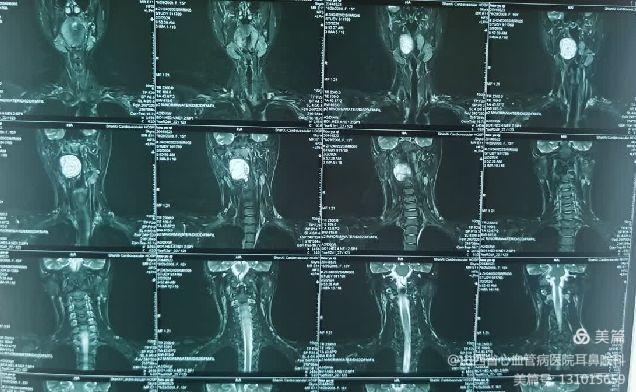

患儿就诊时,自觉偶有憋气及咽痛。张浩杰主任第一时间接诊,经过仔细查体、喉镜和颈部影像学CT与MRI检查后,发现患儿咽腔明显受压,口咽部椎前间隙巨大肿瘤。